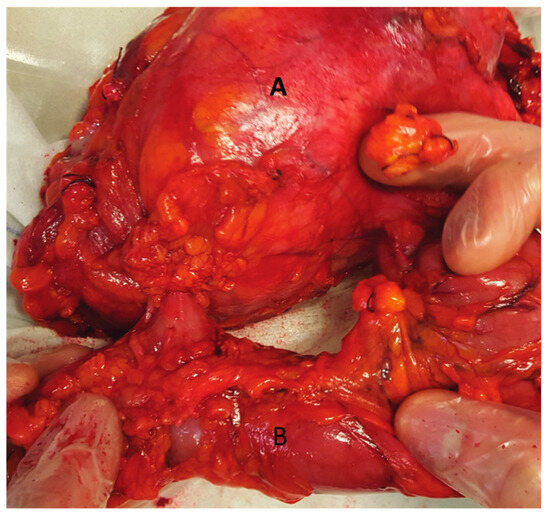

Our 65-year-old patient reported repeated renal colic, with air emission during urination, and presented with a pyelo-colic fistula (Figure 1 and Figure 2). Radical treatment was carried out. The anatomo-pathological analysis showed a chronic pyelonephretic kidney abscessed. with a destroyed kidney.

Figure 2.

One-piece resection: native left kidney (A) with fistula tract facing the left colon (B).